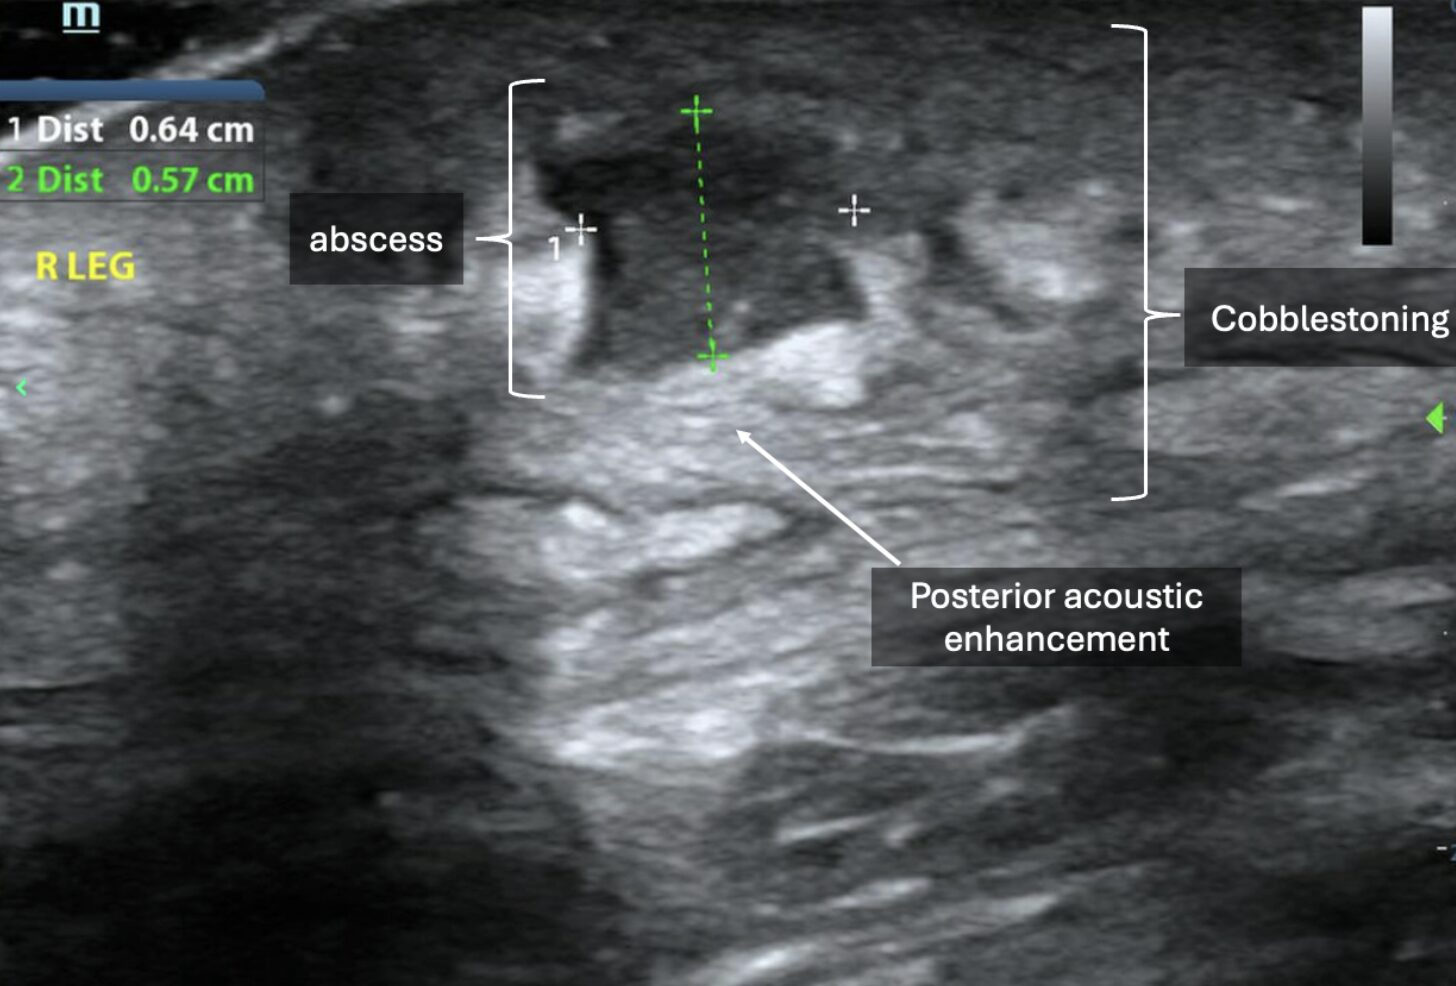

Sonographically, abscesses appear as collections of anechoic, hypoechoic, or heterogeneous material depending on the contents of the purulence. Often, there is notable posterior acoustic enhancement deep to these collections (Images 7-8, Video 6-7). Surrounding cobblestoning, as seen in cellulitis, may also be present. When downward, axial pressure is applied to the abscess using the probe, contents within the abscess may demonstrate a dynamic swirling motion referred to as “the squish sign” or “pus-istalsis” (Video 9).

Image 7: Small, hypoechoic collection of material with posterior acoustic enhancement and adjacent cobblestoning. Images courtesy of Dr. Shepherd and Dr. Alerhand.